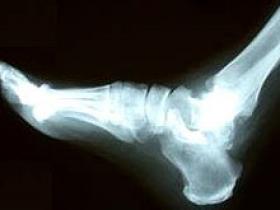

Con el objetivo de apoyar a la población en la pesquisa precoz de la osteoporosis, la Unidad de Endocrinología de Clínica Indisa realizará en forma gratuita densitometrías óseas de talón los días 21, 22 y 23 de julio.

Considerando este hecho, y dada la importancia de un diagnóstico temprano, se recomienda someterse a una densitometría ósea a hombres y mujeres mayores de 40 años con antecedentes previos de fracturas, tabaquismo, sedentarismo y uso prolongado de corticoides, entre otros factores de riesgo.